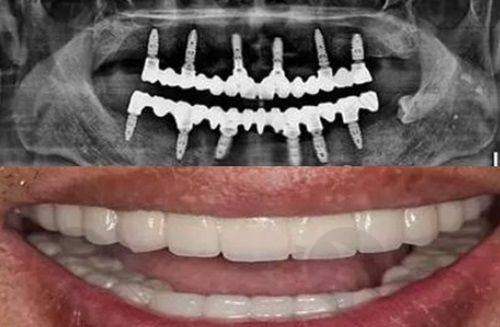

广州友睦猎德口腔门诊部成立于2017年,是一家独立经营的私立口腔医疗机构,位于广州市天河区,面积达800平方米。该院以其综合性的口腔服务赢得了良好的口碑,提供包括种植牙、牙齿矫正、牙周病治疗等多项服务,并配备先进的医疗设备。友睦齿科拥有一支高素质的医疗团队,致力于为患者提供个性化的诊疗服务,确保医疗靠谱与高效率。

广州友睦猎德口腔门诊部擅长项目: 牙套、洗牙、牙周治疗、拔牙、补牙、儿童牙科、地包天